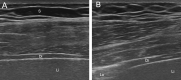

Case presentation: A 51-year-old Caucasian woman was diagnosed with SLE and secondary Sjögren's syndrome based on a history of pleuritis, constrictive pericarditis, polyarthritis, photosensitivity, alopecia, oral ulcers, xerophthalmia and xerostomia. Serologies were significant for positive antinuclear antibodies, anti-SSA, lupus anticoagulant and anti-cardiolopin. Blood work revealed a low C3 and C4, lymphopenia and thrombocytopenia. She was treated with with low-dose prednisone and remained in remission with oral hydroxychloroquine. Seven years later, she developed mild proximal muscle weakness and exertional dyspnea. Pulmonary function testing revealed a restrictive pattern with small lung volumes. Pulmonary imaging showed elevation of the right hemidiaphragm without evidence of interstitial lung disease. Diaphragmatic ultrasound was suggestive of profound diaphragmatic weakness and dysfunction. Based on these findings, a diagnosis of SLS was made. Her proximal muscle weakness was investigated, and creatine kinase (CK) levels were normal. Electromyography revealed fibrillation potentials in the biceps, iliopsoas, cervical and thoracic paraspinal muscles, and complex repetitive discharges in cervical paraspinal muscles. Biceps muscle biopsy revealed dense endomysial lymphocytic aggregates rich in CD20 positive B cells, perimysial fragmentation with plasma cell-rich perivascular infiltrates, diffuse sarcolemmal upregulation of class I MHC, perifascicular upregulation of class II MHC, and focal sarcolemmal deposition of C5b-9. Treatment with prednisone 15 mg/day and oral mycophenolate mofetil 2 g/day was initiated. Shortness of breath and proximal muscle weakness improved significantly.